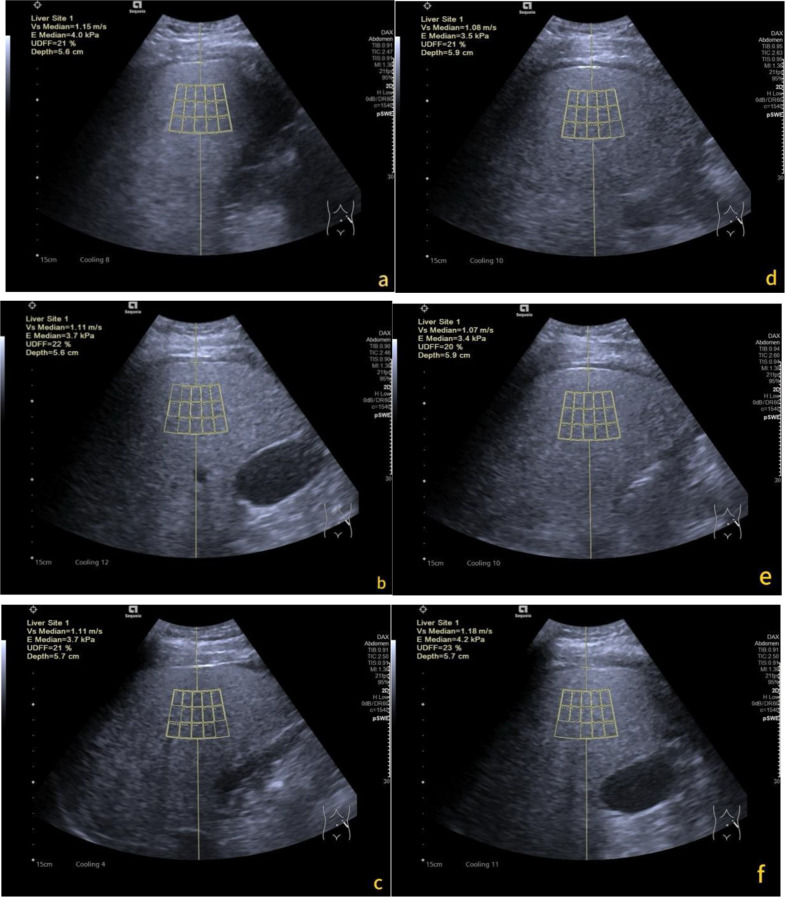

Consistency and reliability of ultrasound-derived fat fraction in hepatic steatosis assessment: influence of posture and breathing variations.